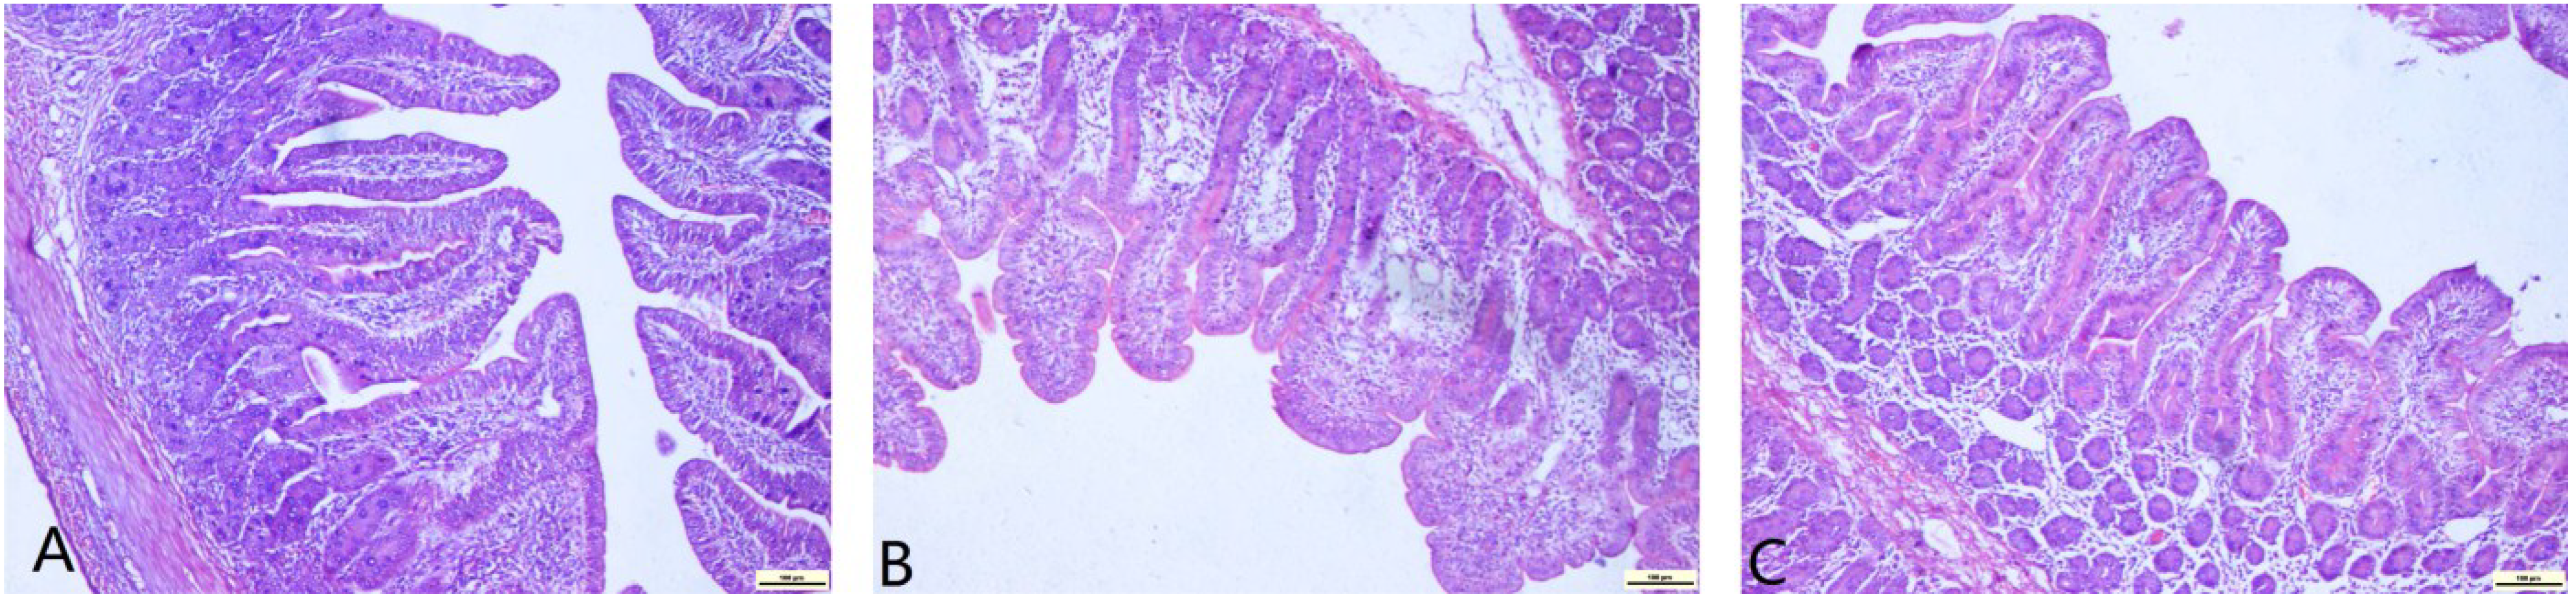

2.4. Jejunal Morphology Changes

Pathological changes (Table 5) and deformation of enterocytes (Figure 1) in the mucosa were observed after the DON-infected diet was fed to pigs. Of note, only slight changes were found in the DON + ARG group. The villus height in the DON group was significantly lower than the other groups. The decrease in the DON + ARG group was mild. No difference was found between the DON + ARG and control groups (p < 0.05). No significant changes were found in crypt depth among the three groups of pigs. The ratio of villus height to crypt depth in the DON group was the lowest. This ratio in the DON + ARG group was slightly decreased compared to the control group (p > 0.05).

Figure 1.

Effects of DON exposure on histopathology in the jejunum of weanling pigs: (A) normal histological structure in pigs fed the control diet; (B) severely impaired enterocytes in pigs fed the 6 mg/kg DON diet; (C) mild impairment of enterocytes in pigs fed the 6 mg/kg DON + 1% arginine diet. Original magnification: 400× (n = 6). All the scale bars in figures A to C represent 100 µM.

DON is a common contaminant of cereal crops, like wheat, barley, corn and oats, and of high importance in the food and feed industry and, increasingly, a food safety issue problem worldwide. Some reports suggested that ingestion of DON may induce feed refusal, decreased animal productivity, organ damage, increased disease incidence and malabsorption of nutrients [1,2,3,4,5,6,7,15,16,17]. The integrity of jejunum mucosal morphology and structure is a prerequisite of biological functions [16,17]. The villus height and crypt depth represent the metabolic and mature status of intestinal epithelial cells [18]. We found that DON damaged the integrity of the small intestine, but had no effect on the crypt depth. These results indicated that DON affects intestinal health via other ways, rather than harassing the development of intestinal cells. Meanwhile, no notable differences in the villus height or the value of villus height/crypt depth were found between the DON + ARG and control groups. According to previous studies, Arg supplementation in diet increases the intestinal mucosal thickness and the number of the small intestinal villi [19,20]; Arg stimulates the hypothalamus to release growth hormone, so as to reduce intestinal mucosa atrophy, accelerate injury recovery and maintain the structure and function of the intestinal mucosa [21]. We, therefore, conclude that Arg ameliorates the changes of the intestinal mucosal morphology and structure caused by DON.